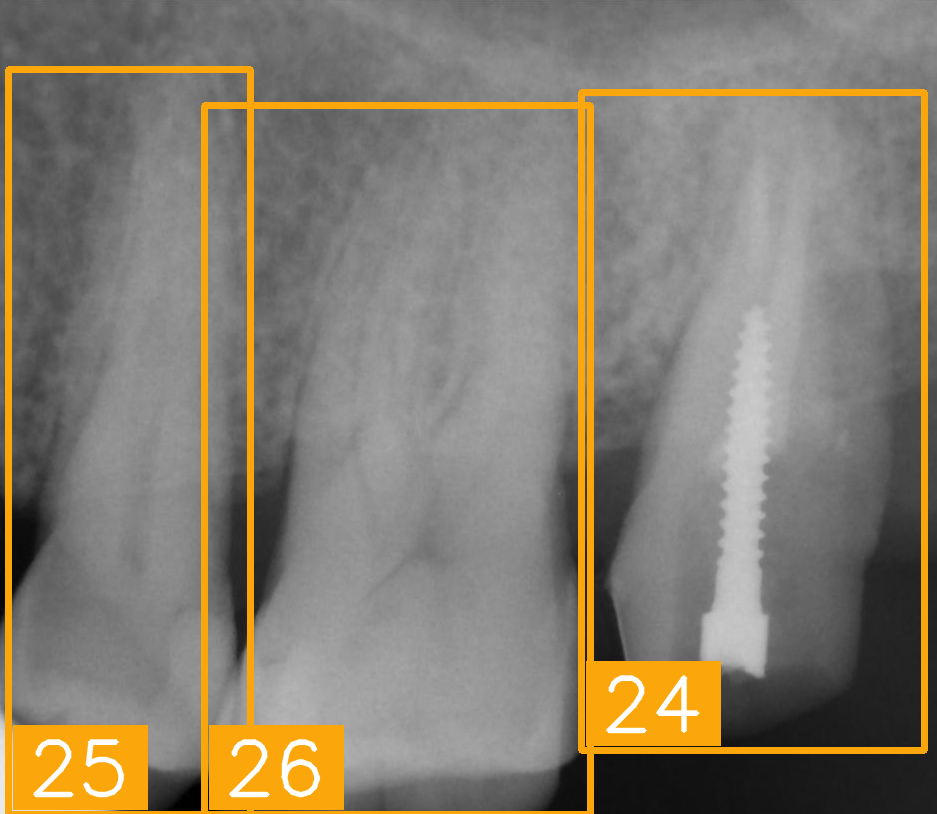

| Number | (a) | (b) | (c) | (d) |

| Condition | Fractured tooth; Implant | Overlaapping | Missing Tooth | Incomplete crown |

| PA | ![]() | ![]() | ![]() | ![]() |

| FDI ground truth number | 23, 24, 25, 26 | 43, 42, 41, 31, 32, 33 | 12, 11, 21, 22 | 44, 43, 42, 41, 31, 32 |

| Inference Time | 75.9 ms | 73.3 ms | 76.1 ms | 69.9 ms |

| Number | (e) | (f) | (g) | (h) |

| Condition | Fractured tooth; lower brightness | Overlapping | Implant | Implant |

| FDI ground truth number | 45, 44, 43 | 32, 33, 34, 35 | 16, 15, 14, 13, 12 | 24, 25, 26 |

| Inference Time | 72.8 ms | 77.2 ms | 70.6 ms | 72.4 ms |